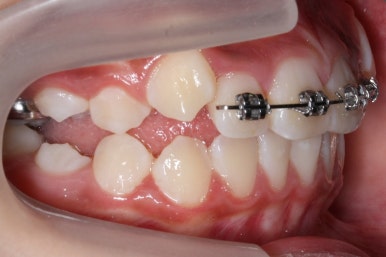

골격분석과 X-ray 등으로 확인했을 때, 이번 환자분은 위턱이 약간 상대적으로 나와있다고 판단이 되었습니다. 위쪽 치열은 아래쪽 보다 앞으로 나와있으며 특히 어금니가 앞쪽으로 나와있었어요.

따라서 교정계획은 헤드기어를 사용해 위쪽 어금니는 뒤로 밀고 영구치가 추후 맹출이 될 때 까지 시간을 주자는 것이였어요.

최대한 비발치로 연산동덧니교정을 하자는 판단이며 성장기에는 공간만 충분하다면 삐뚤했던 치아도 자리를 어느정도 잡기 때문입니다.

위쪽 어금니를 뒤로 밀어주기 위해 헤드기어라는 장치를 사용했습니다.

어금니쪽은 둘러 싸고 앞니는 별도로 가지런하게 해주는 작업이죠.